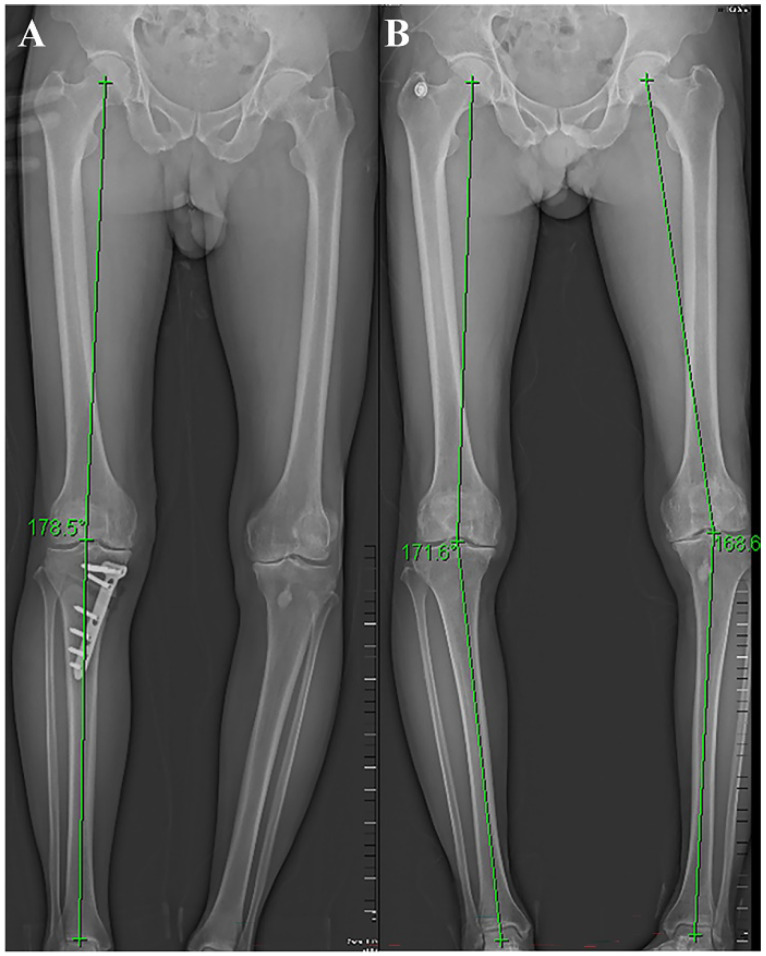

High tibial osteotomy (HTO) has been widely applied in clinical practice to treat unilateral knee osteoarthritis (OA). In order to improve the effectiveness of surgical treatment, researchers attempted to use a combination of platelet-rich plasma (PRP) and HTO therapy. We summarized the clinical outcomes of engaging HTO and PRP and found promising clinical advantages in improving postoperative pain and function, promoting cartilage repair, and increasing bone cartilage structure in patients. Further studies are needed to provide more convincing evidence of the efficacy of the combined therapy.